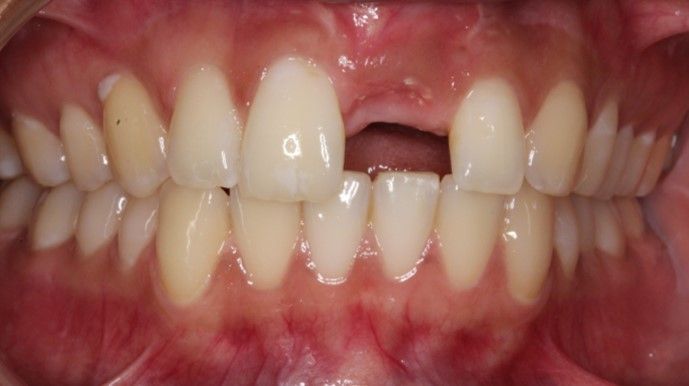

Case 1 - Upper incisor and bone loss due to root fracture after trauma to the tooth. Replaced with dental implant and simultaneous bone grafting